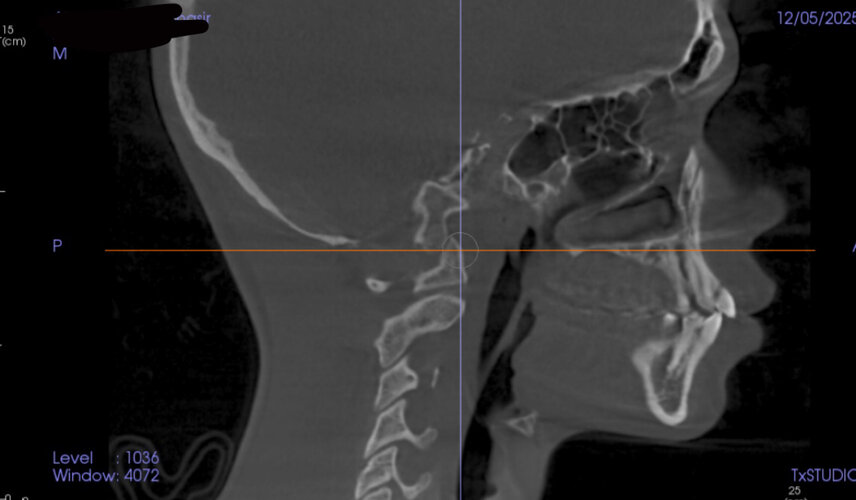

Went to the orthodontist the other day and got these scans. I’m trying to figure out what I should change or improve to look better. Based on this, what do you think needs work and what can I do to improve it?